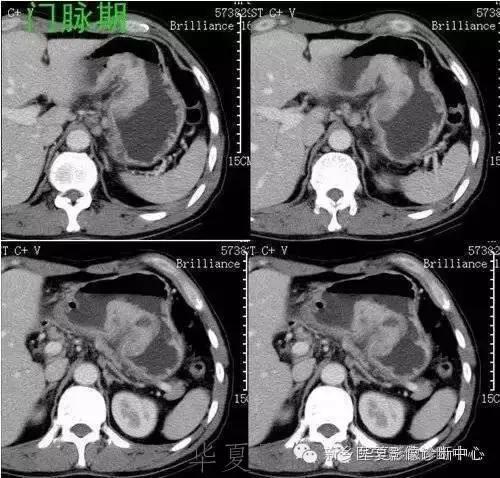

肝脏黑色素瘤

原发于肝脏的恶性黑色素瘤极其罕见。肝脏原发恶性黑色素瘤临床表现及体征均无特征性,与其他肝脏占位性、 肿瘤性病变无法区分,此为该病的临床特征。

肝脏恶性黑色素瘤的超声和 CT多表现为肝脏增大,肝内单发、 多发占位病变或弥漫性、 结节性改变, 占位性病变可为实性、 囊性、 囊实性改变,但上述改变无明显特异性, 与其他肝脏恶性肿瘤无法区分。MR T1 加权呈高信号、 T2 加权呈低信号